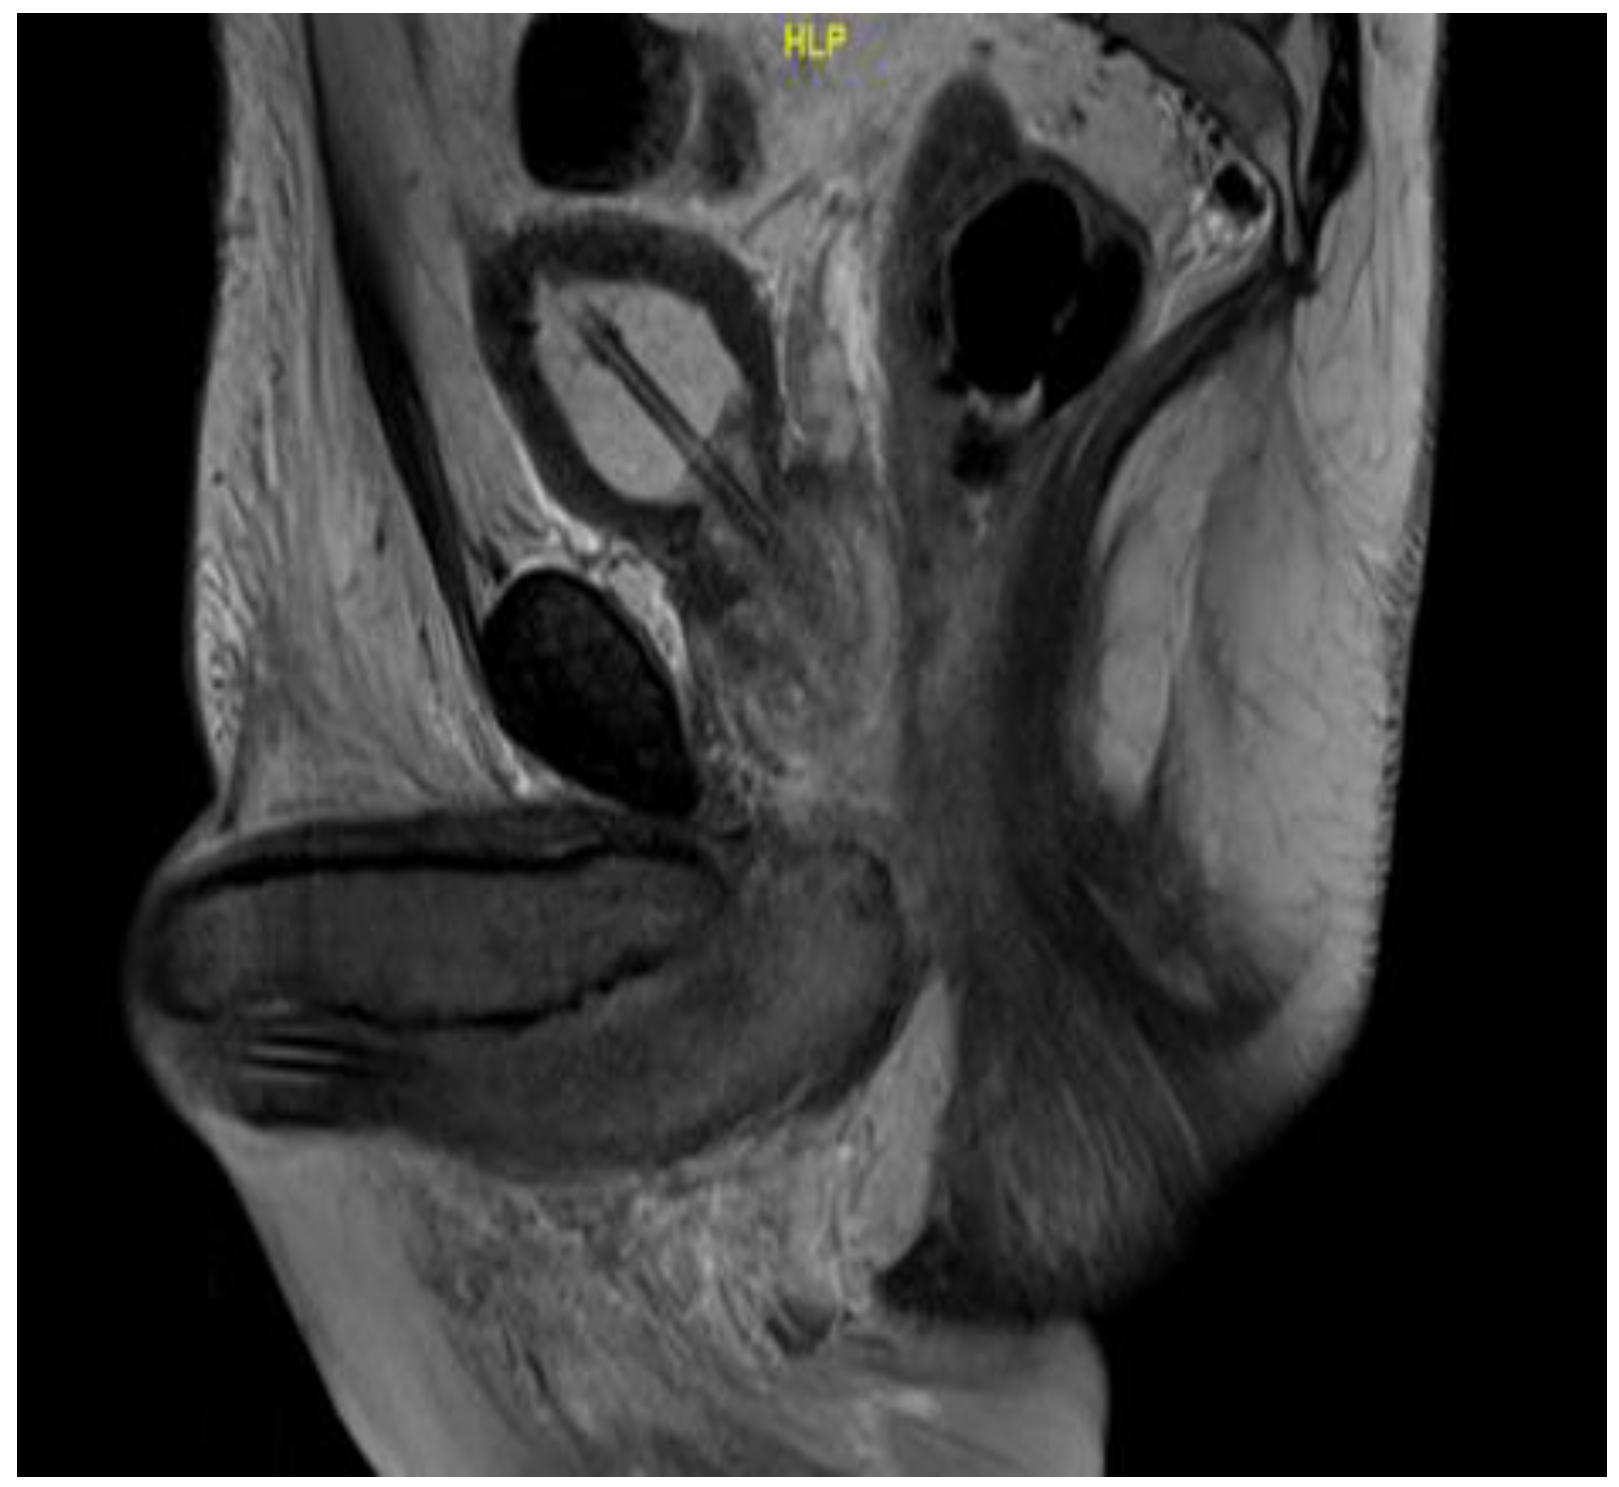

Figure 2.

Sagittal MRI T2 scan showing enlarged bulbospongiosus.